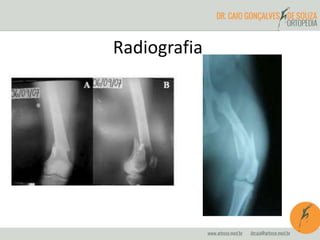

Radiografia

Tratamento

Conservador Cirúrgico